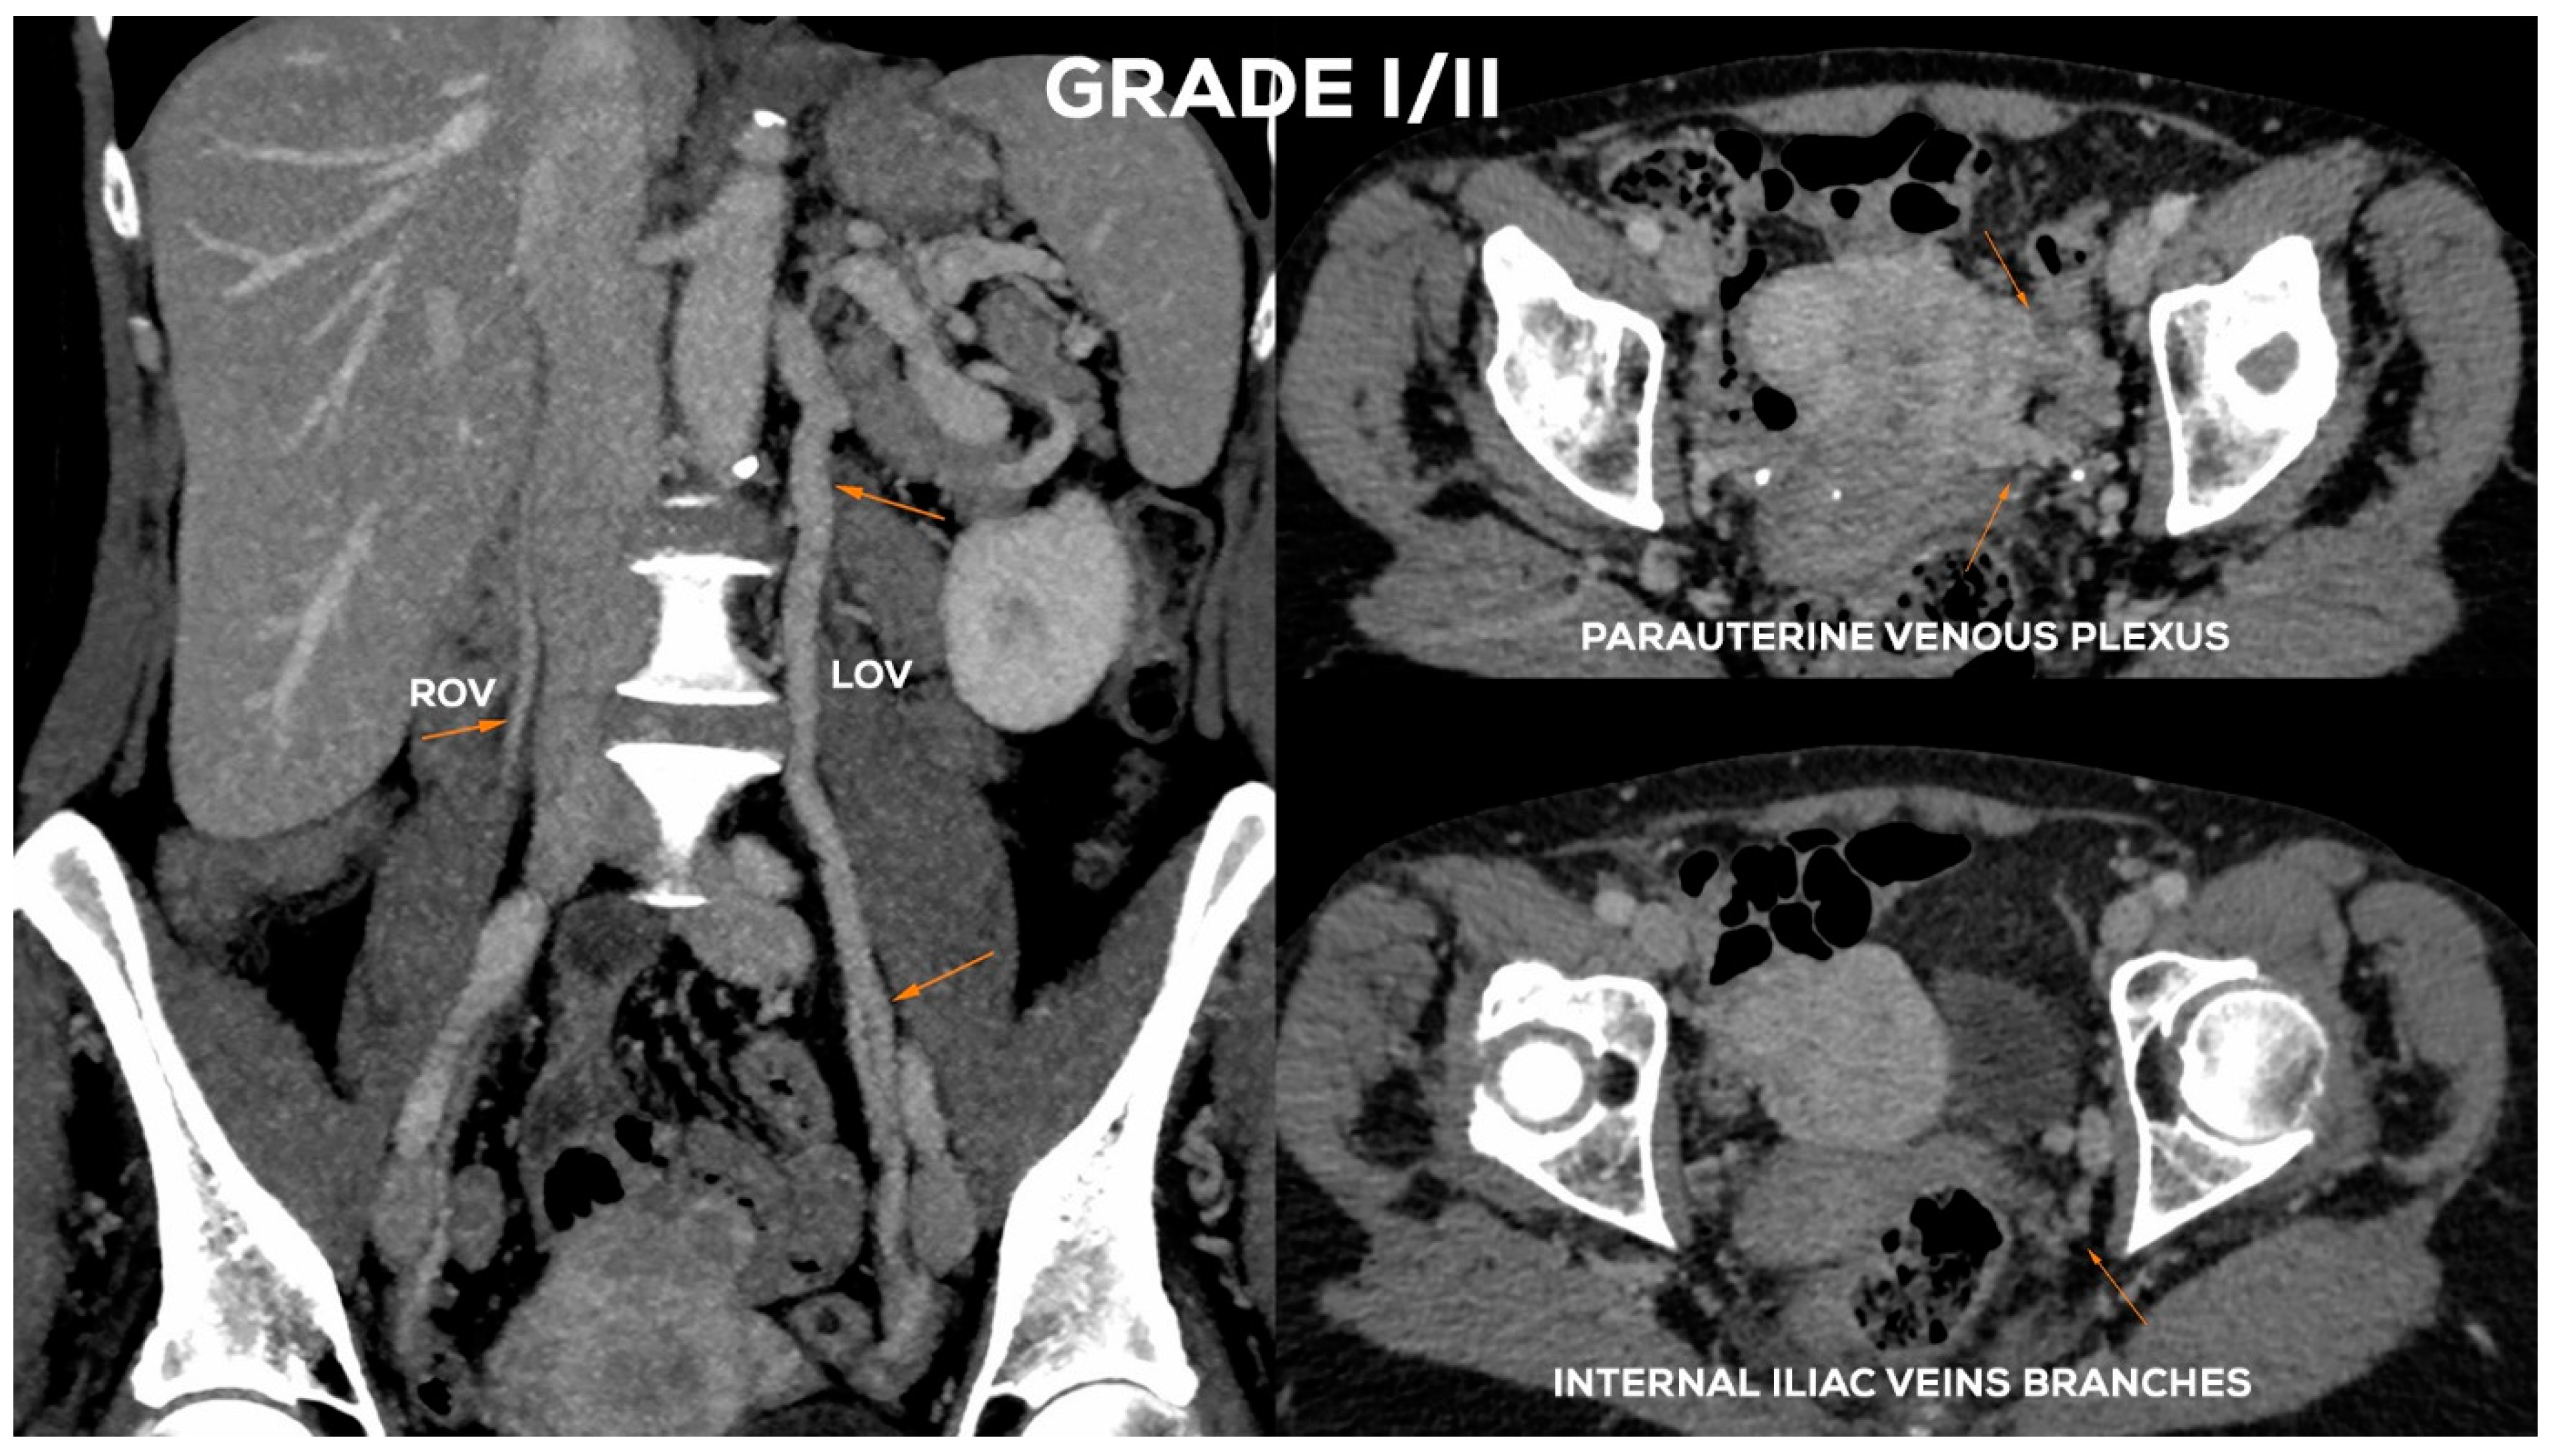

Figure 12.

Typical findings in patient with Grade II ovarian veins insufficiency seen on a CTV images in coronal and axial planes.